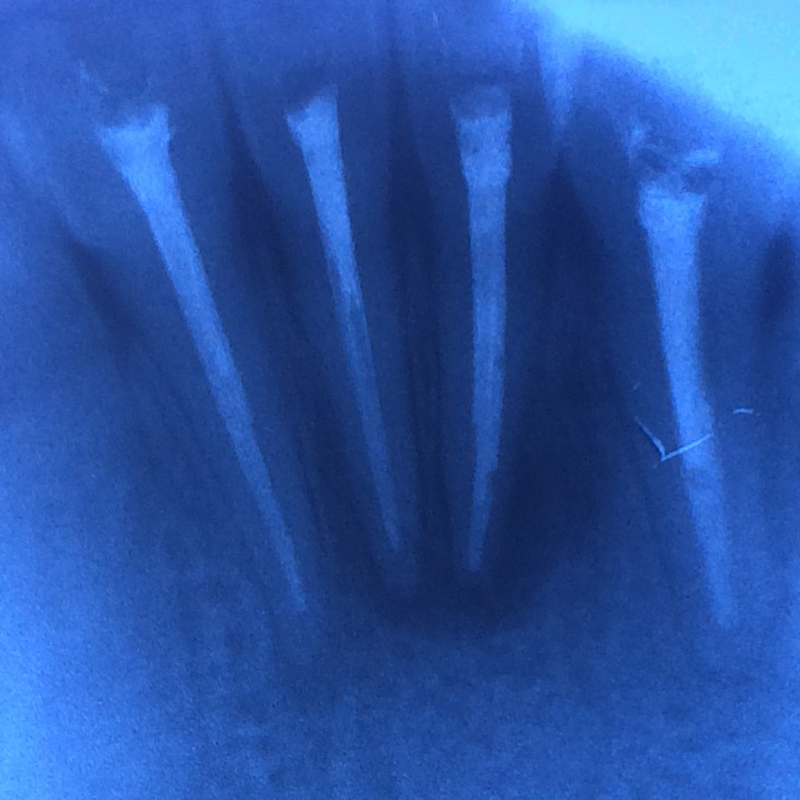

До и после лечения

Пациент обратился в «Стоматологию Комфорта» с жалобой на острую боль в области нижних резцов, возникшую после начала лечения в другой клинике. В ходе осмотра и по результатам диагностики врач стоматолог-терапевт Вахлюева Елена Сергеевна поставила диагноз — периодонтит в стадии обострения.

В процессе лечения проведены следующие манипуляции:

- эндодонтическое лечение зубов 3.1, 3.2, 4.1, 4.2;

- пломбировка корневых каналов;

- временное восстановление коронковой части зубов.